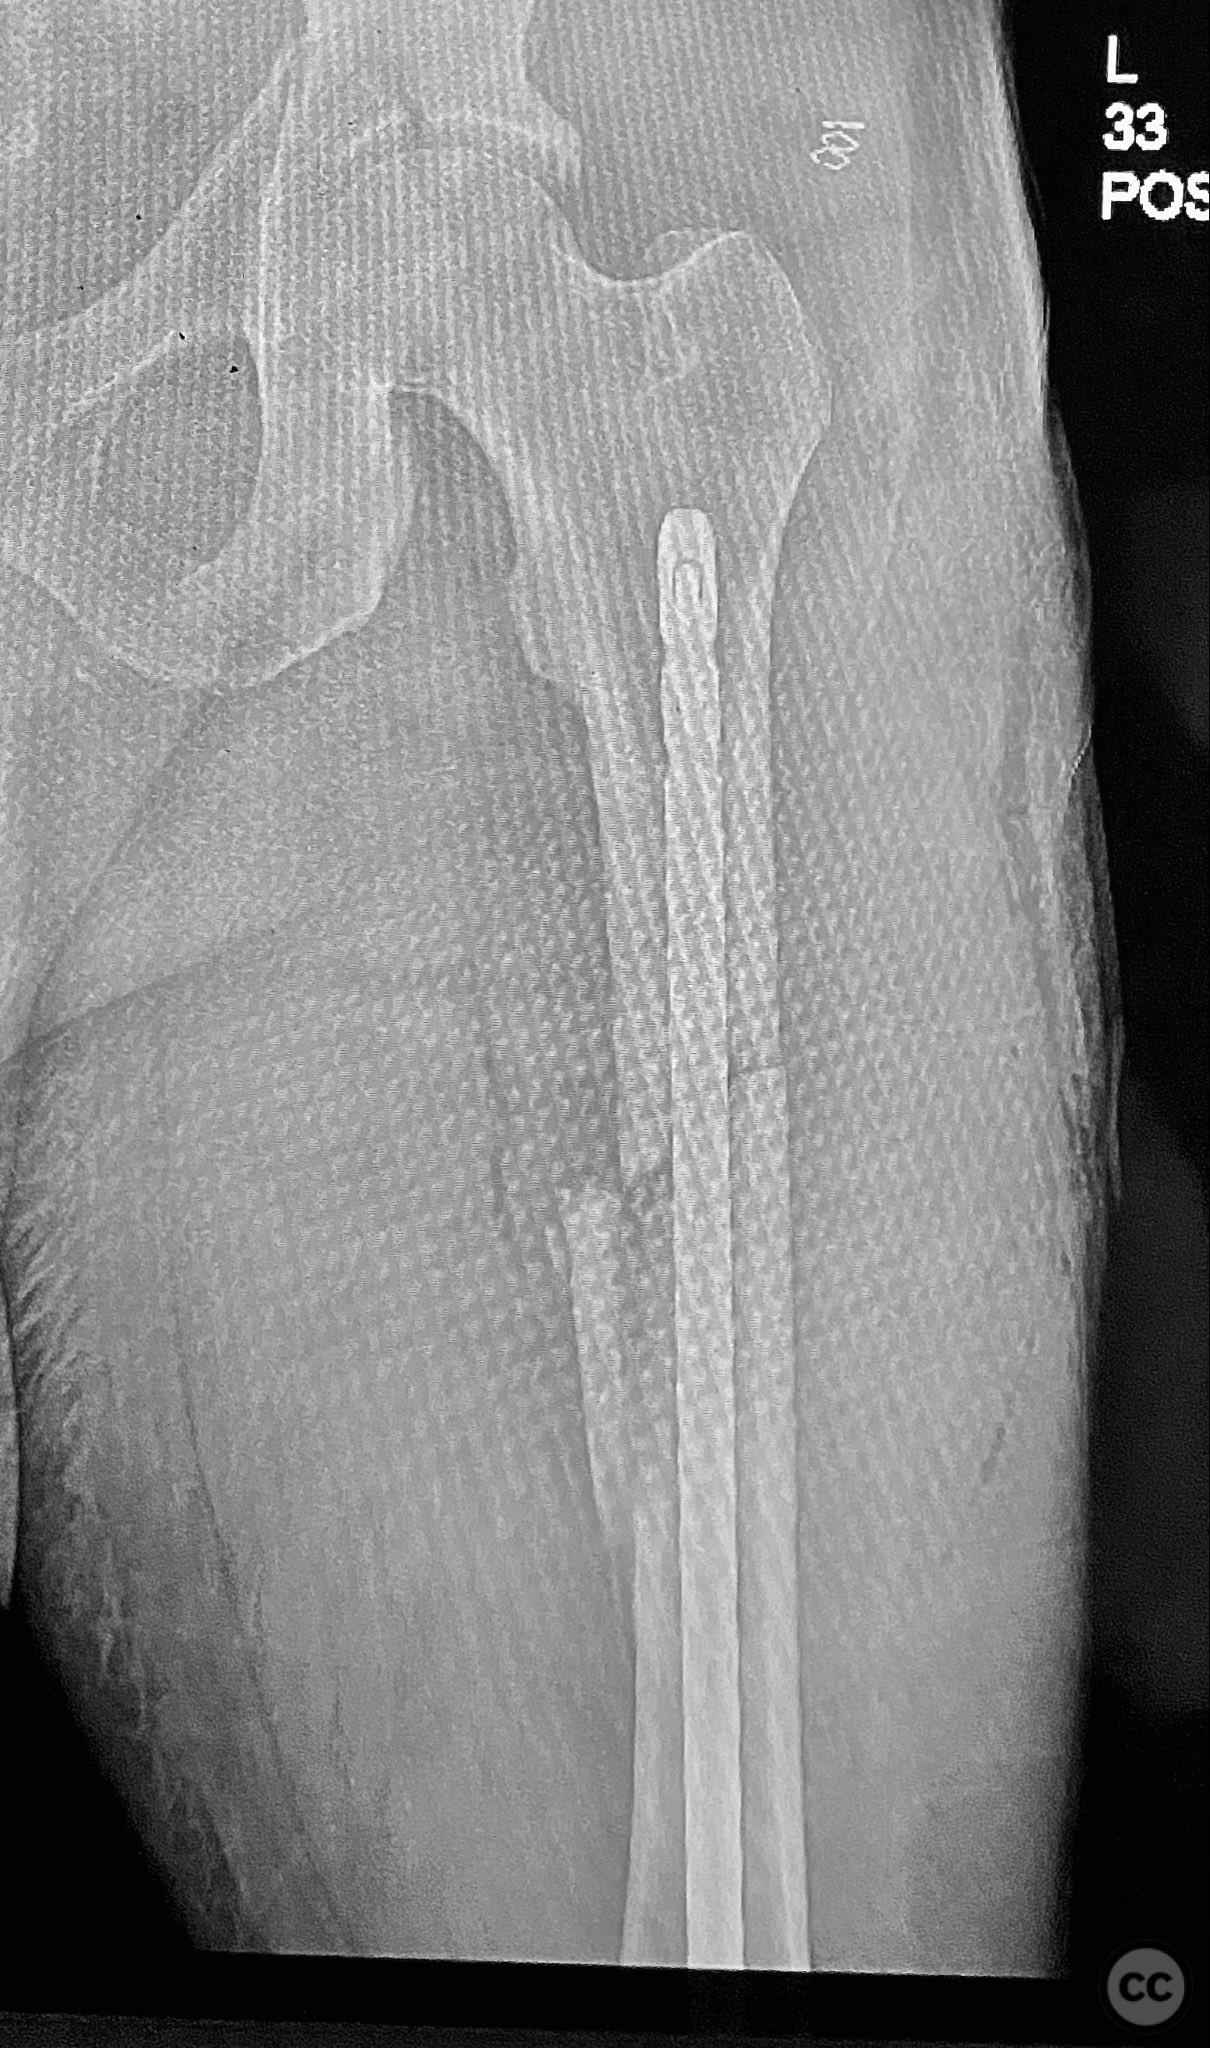

Clinical and radiological findings:  Adult male with a closed, comminuted left femoral shaft fracture and complex pelvic ring injury. Initial imaging demonstrated bilateral sacroiliac (SI) joint disruptions and a left-sided transtectal transverse acetabular fracture (Letournel-Judet: transverse type), with the fracture line exiting through the posterior wall region but without a discrete posterior wall fragment. The femoral head was displaced caudally, following the unstable distal acetabular segment, resulting in loss of congruency with the intact acetabular dome. There was also a symphyseal disruption. No associated abdominal, visceral, thoracic, cranial, or other injuries were present. Application of a circumferential pelvic binder resulted in visible changes in pelvic alignment on imaging. AO/OTA Classification: - Pelvic ring: 61-C1.3 (bilateral SI joint disruption, complete instability) - Acetabulum: 62-B1 (transverse fracture) - Femur: 32-C3 (comminuted diaphyseal fracture)

Planning remarks:  The preoperative plan involved staged management: initial resuscitation and provisional stabilization with a circumferential pelvic binder, followed by operative reduction and fixation of the pelvic ring using an anterior two-pin external fixator for SI joint compression and reduction, percutaneous iliosacral (IS) and transsacral (TS) screw fixation, and subsequent intramedullary nailing of the femur. Definitive acetabular fixation was planned via a posterior Kocher-Langenbeck approach in the prone position.

Orthopaedic implants used:   - Anterior two-pin external fixator - Percutaneous iliosacral screw(s) - Percutaneous transsacral screw(s) - Intramedullary femoral nail - 4.5 mm cortical screws (acetabular fixation) - Posterior column reconstruction plate(s)